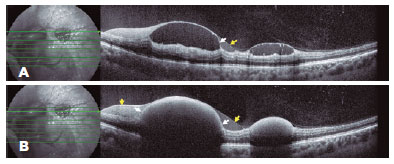

OCT (Spectralis Heidelberg Engineering, Heidelberg, Germany) of the LE revealed multiple subhyaloid and sub-internal limiting membrane (ILM) hemorrhages of variable size in the posterior pole and periphery near the vascular arcades (Figure 2). Fluorescein angiography revealed only blocking effect of the hemorrhages (Figure 1B).